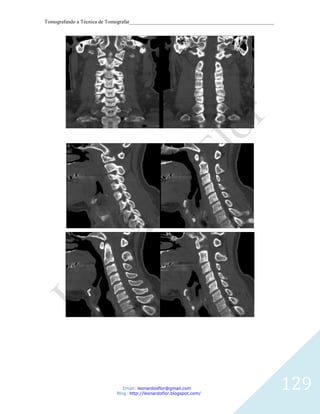

Tomografando a Técnica de Tomografar_______________________________________________________

ESPAÇO CERVICAL ANTERIOR: estende-se desde o osso hióide até a clavícula e está

preenchido por gordura. A fáscia visceral o separa do espaço visceral medialmente; a

camada superficial da fáscia cervical profunda limita o espaço ântero-lateralmente e a

bainha carotídea o limita posteriormente. O espaço submandibular está situado

superiormente, sem separação por planos fasciais.

Lesões: lipoma, cisto branquial, abscesso e linfangioma

TÉCNICA DE EXAME

O paciente é deitado na mesa de exames e lentamente será levado para o interior do gantry,

onde serão feitas as imagens da região cervical. É muito importante permanecer imóvel e

seguir as instruções do profissional que realizará o exame. O tempo de exame é variável,

podendo durar de 5 a 20 minutos.

Em relação ao preparo este exame requer um jejum absoluto (inclusive de água) de quatro

horas, cliente deve suspender, nas 48 horas que antecedem o exame e com o consentimento

do médico assistente, o uso de medicamentos que contenham a metformina (Dimefor®,

Glifage®, Glucoformin®, Glucovance® ou Starform®) e a fenformina (Debei®), que é

contraindicado nos exames com contraste iodado endovenoso. A suspensão dessas

medicações ainda precisa ser mantida por 48 horas após o exame.